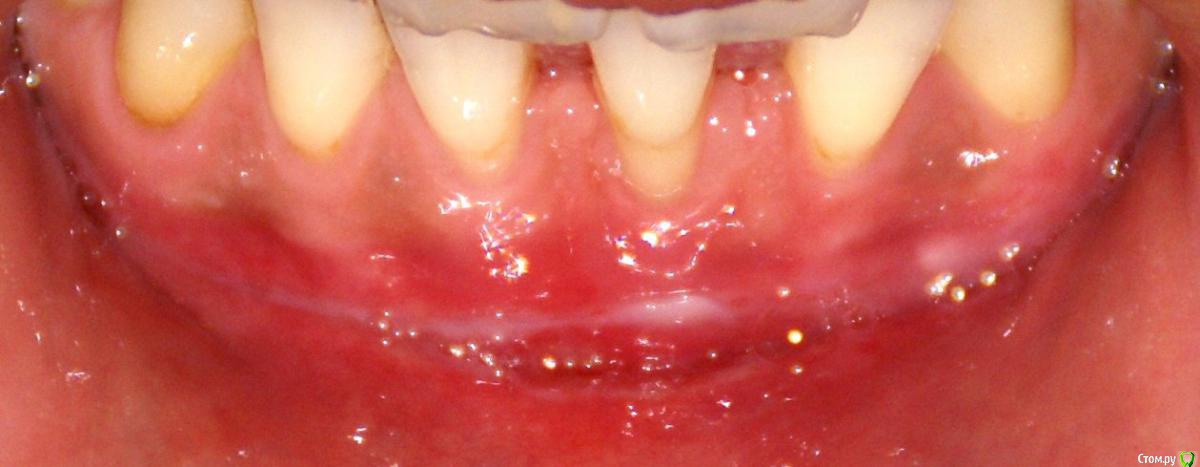

Irina_S Опубликовано 15 июня, 2017 Поделиться Опубликовано 15 июня, 2017 Здравствуйте, уважаемые специалисты! Заранее прошу прощения за не слишком качественные фото! Почти восемь месяцев назад мне была сделана вестибулопластика на нижней челюсти.За пять дней до операции ситуация во рту выглядела так: Для проведения операции были такие показания: Вот ещё описание самой операции, которая была 24 октября 2016 г.: Через шесть дней после операции: Ещё через шесть дней, 5 ноября: Прошла ещё неделя, 12 ноября: Следующий раз фото, к сожалению делалось через три с лишним недели, 4 декабря, в разных ракурсах: После этого визуальные изменения касались только уменьшения белёсых мест от разреза.Вот состояние на 10 июня этого года с разными вариантами оттягивания губы: По результатам заживления я не вижу разницы в глубине преддверия, ради чего и проводилась операция.К тому же всё время с момента операции присутствуют стягивающие ощущения и ощущение инородного тела в подбородке. Ответьте, пожалуйста, правильно ли была сделана операция вестибулопластики?Спасибо за внимание! Ссылка на комментарий